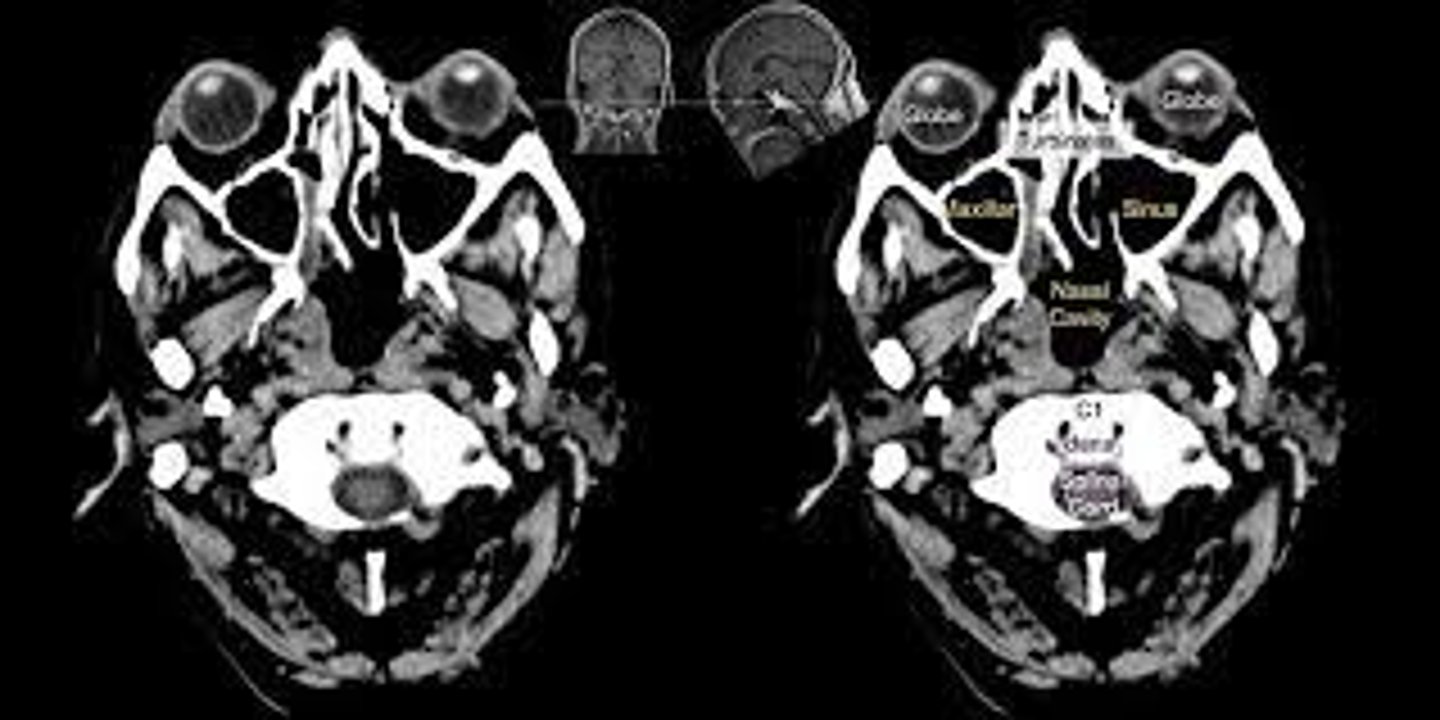

CBCT

ID the type of Imaging modality:

- Pano

- CT

- CBCT

- MRI

- Technetium 99 bone scans

- PET

axial

ID the plane of view: